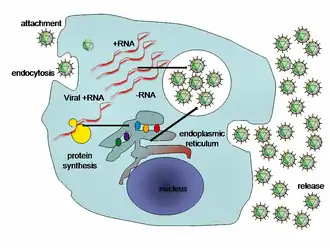

Viral hepatitis

Viral hepatitis is the most common type of hepatitis worldwide, especially in Asia and Africa.[27] Viral hepatitis is caused by five different viruses (hepatitis A, B, C, D, and E).[18] Hepatitis A and hepatitis E behave similarly: they are both transmitted by the fecal–oral route, are more common in developing countries, and are self-limiting illnesses that do not lead to chronic hepatitis.[18][28][29]

Hepatitis B, hepatitis C, and hepatitis D are transmitted when blood or mucous membranes are exposed to infected blood and body fluids, such as semen and vaginal secretions.[18] Viral particles have also been found in saliva and breastmilk. Kissing, sharing utensils, and breastfeeding do not lead to transmission unless these fluids are introduced into open sores or cuts.[30] Many families who do not have safe drinking water or live in unhygienic homes have contracted hepatitis because saliva and blood droplets are often carried through the water and blood-borne illnesses spread quickly in unsanitary settings.[31]

Viral hepatitis

The pathway by which hepatic viruses cause viral hepatitis is best understood in the case of hepatitis B and C.[18] The viruses do not directly activate apoptosis (cell death).[18][60] Rather, infection of liver cells activates the innate and adaptive arms of the immune system leading to an inflammatory response which causes cellular damage and death, including viral-induced apoptosis via the induction of the death receptor-mediated signaling pathway.[18][60][61][62] Depending on the strength of the immune response, the types of immune cells involved and the ability of the virus to evade the body's defense, infection can either lead to clearance (acute disease) or persistence (chronic disease) of the virus.[18] The chronic presence of the virus within liver cells results in multiple waves of inflammation, injury and wound healing that over time lead to scarring or fibrosis and culminate in hepatocellular carcinoma.[60][63] People with impaired immune response are at greater risk of developing chronic infection.[18] Natural killer cells are the primary drivers of the initial innate response and create a cytokine environment that results in the recruitment of CD4 T-helper and CD8 cytotoxic T-cells.[64][65] Type I interferons are the cytokines that drive the antiviral response.[65] In chronic Hepatitis B and C, natural killer cell function is impaired.[64]